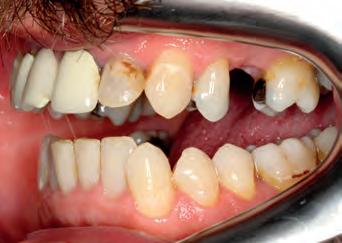

Patient: face before

A53 year old man attended complaining of pain from an existing bridge UR2 - UL2. It needed to be extracted because several roots were infected and would have required re-RCT, which the patient did not want to do. On closer inspection, the remaining teeth in the upper arch required some work as well (one RCT), but otherwise the teeth had a good prognosis.

The options were explained to the patient (implants, bridges/crowns/dentures) and the patient decided to save his remaining teeth. Written and verbal consent was obtained. We took clinical records and a series of DSLR photos and intraoral scanning with the Carestream 3600 intra oral scanner with scan flow software. The CS 3600 was chosen because of the comprehensive restorative features such as checking how much tooth structure has been removed compared to the pre-op tooth shape, as well as checking for any undercuts.

The decision was made, to extract the remaining upper incisors and make a temporary bridge from UR3 - UL3 in Luxatemp A3 with no immediate change to tooth shape or smile design.

TOP ROW: Before lower occlusal, Before retracted in occlusion 2ND ROW: Before retracted left in occlusion, Before retracted left open 3RD ROW: Before retracted open, Before retracted right in occlusion 4TH ROW: Before retracted right open, Before upper occlusal